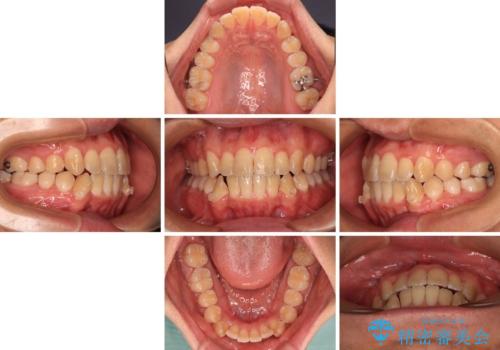

- 前歯の開咬を気にして来院された患者様です。

開咬の治療は、前歯を閉じるように動かすとともに、上下臼歯を圧下(骨内にめり込ませる)させることで進めて行きます。

インビザラインは臼歯の圧下を効果的に行えるため、インビザラインを用いて矯正治療を行うこととしました。

オープンバイトは舌の突出癖により誘発され、治療後も突出癖が残っている容易に後戻りしてしまいます。

治療期間を短縮するためにも、舌突出癖の改善が極めて重要となります。

特にインビザラインではIPRという歯と歯の間を削る処置を多用するため、後戻りによりスペースが生じやすくなるため、治療初期段階での舌のトレーニングが必須となります。